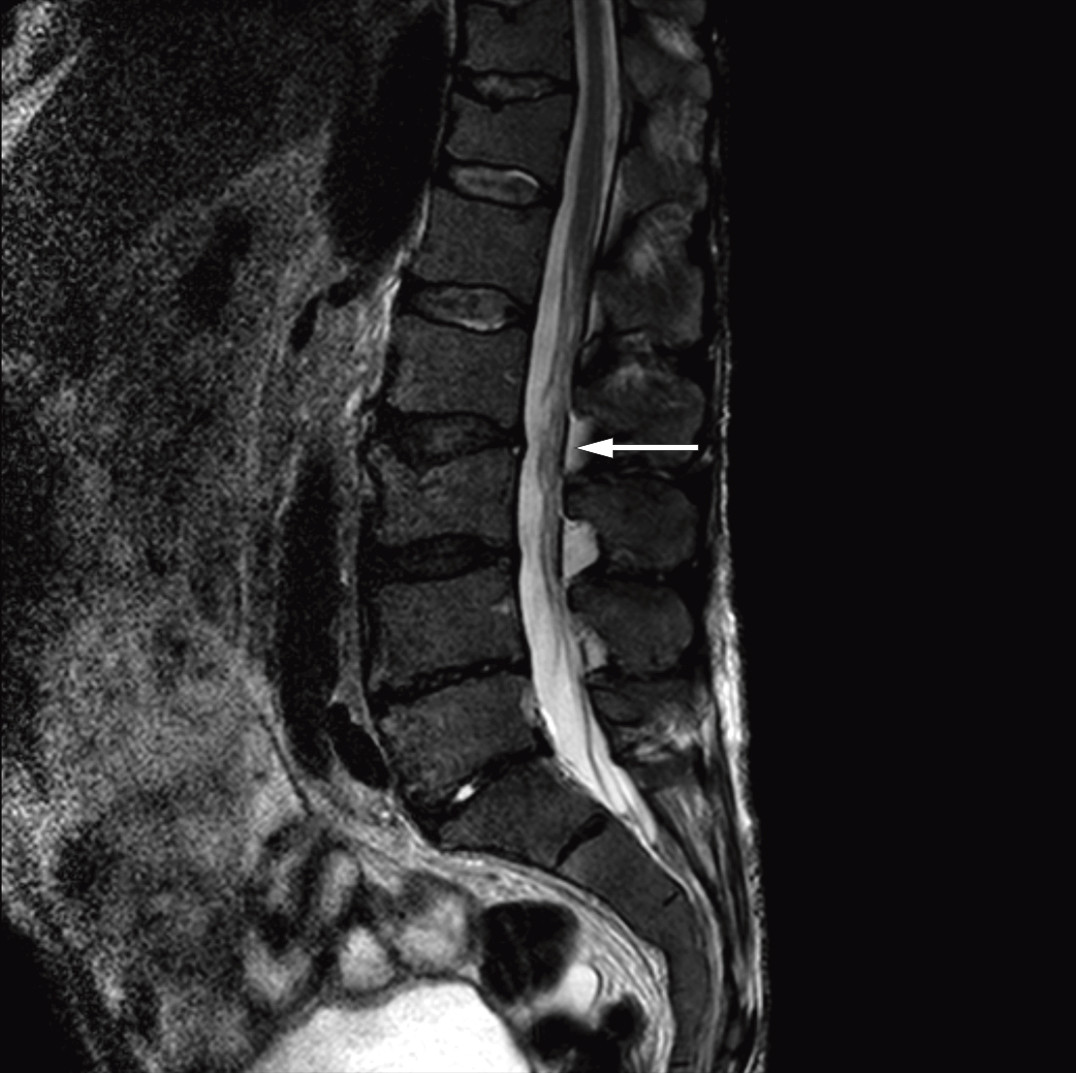

Etter at diagnosen Bing-Neel-syndrom var stilt, gransket vi MR-bildene av cerebrum og lumbosakralcolumna på ny og fant patologisk fortykkede og kontrastladende meninger over begge storhjernehemisfærer (figur 1) og cerebellum samt bølgede og fortykkede cauda equina-røtter (figur 2). Vi konkluderte med at de fortykkede meningene var uttrykk for diffus affeksjon av sentralnervesystemet forenlig med Bing-Neel-syndrom. Funnet av fortykkede cauda equina-røtter ble også antatt å ha sammenheng med syndromet, men det kunne ikke fastslås med sikkerhet siden forandringene var sparsomme, og bildene dessverre ble tatt uten kontrast.